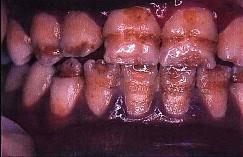

问题 釉质发育不全的临床表现是 ( )

选项 A.釉质表面暗白不透明、无光泽 B.缺损处无软化现象 C.釉质表面呈深度不等的带状或窝状凹陷 D.釉质表面缺损呈现蜂窝状 E.以上均是

答案 E